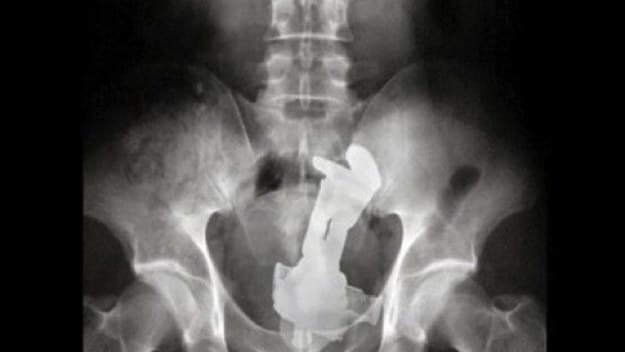

8. Ένα τηλέφωνο